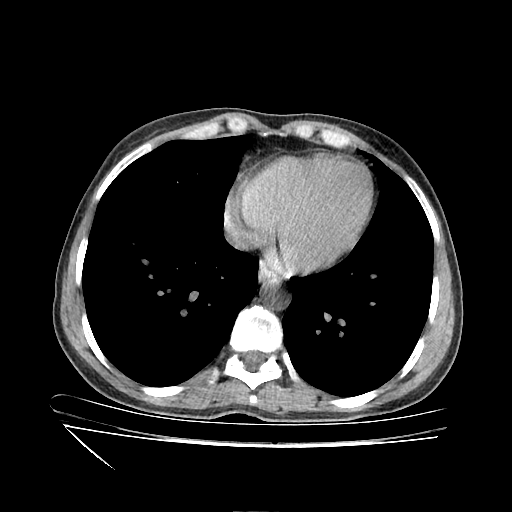

Original VENOUS CT scan

Full window (WL 1023.5, WW 4095 β†’ Low βˆ’1024, High +3071)

Mediastinum window (WL 40, WW 400 β†’ Low βˆ’160, High +240)